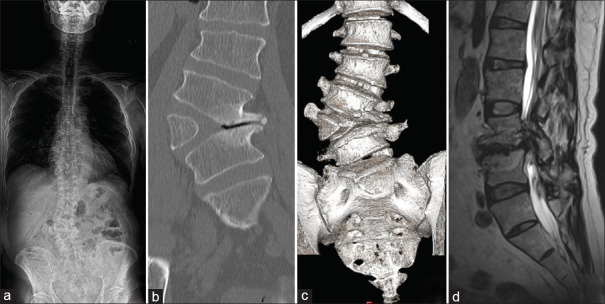

Hemivertebra is a rare congenital spinal anomaly often diagnosed in childhood due to progressive scoliosis. Initial diagnosis of hemivertebra in adulthood is uncommon, and standardized treatment protocols are not well established. This report presents a case of successful management of an L4 hemivertebra in an adult using oblique lateral interbody fusion (OLIF) with O-arm navigation. The patient, a 55-year-old, presented with chronic lower back pain and thigh pain exacerbated by standing and walking. Imaging studies revealed an L4 hemivertebra with mild scoliosis and foraminal stenosis caused by degenerative change. The patient underwent OLIF with O-arm navigation, followed by short-segment fixation with pedicle screws. Postoperative imaging confirmed appropriate implant positioning. The patient experienced complete resolution of symptoms except for mild sensory disturbance in the left thigh, with stable outcomes at the 2-year follow-up. The OLIF technique, guided by O-arm navigation, allowed precise adjustments to the anatomical characteristics of the hemivertebra, minimizing surgical invasion, and avoiding extensive corrective fixation. This approach resulted in favorable outcomes, suggesting its viability as a treatment for adult hemivertebra with minimal scoliosis. Furthermore, the use of intraoperative navigation addressed the anatomical abnormalities associated with adult hemivertebra, reducing the reliance on repeated fluoroscopic imaging and minimizing the risk of complications. OLIF with O-arm navigation is an effective and minimally invasive treatment option for adult hemivertebra, providing symptom relief and favorable outcomes.